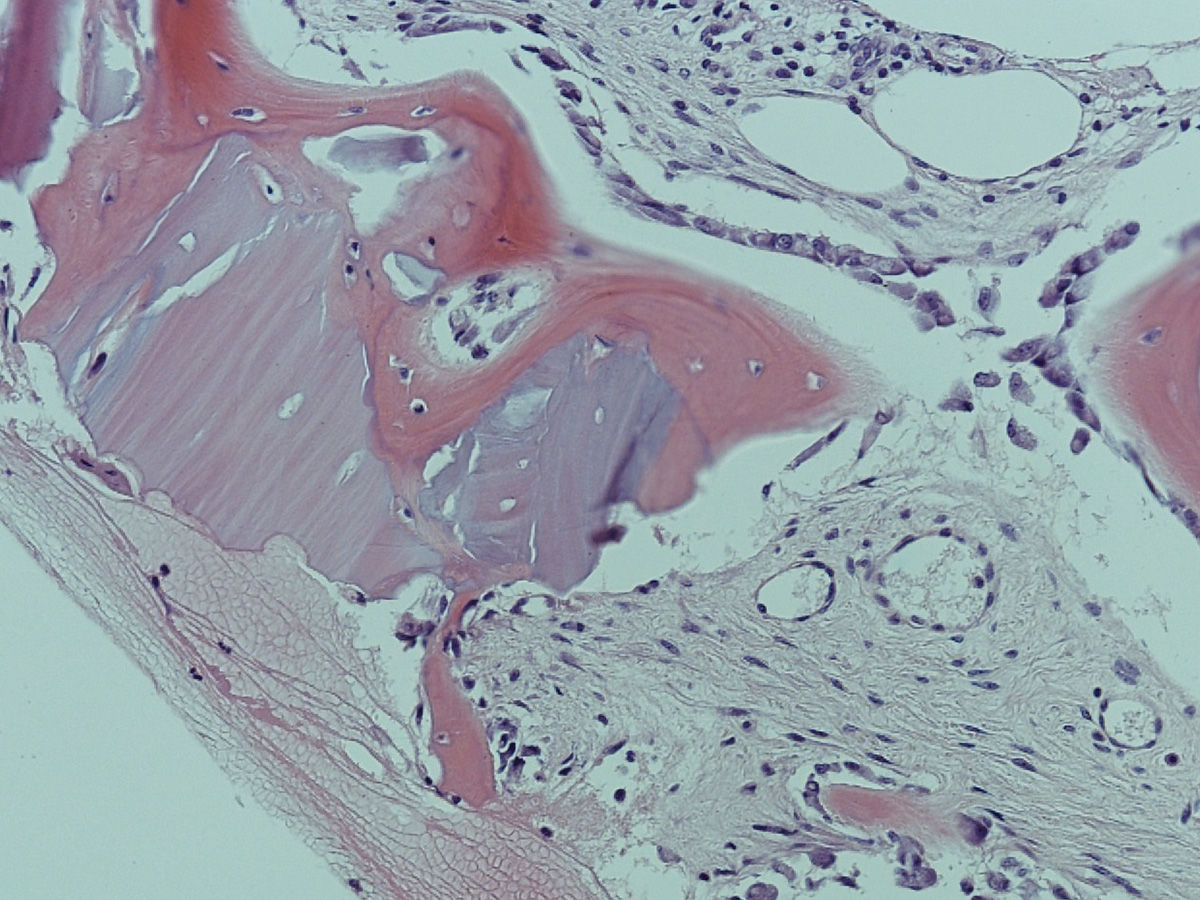

Biopsate aus der Maxilla, Entnahme nach vier Monaten.

Abbildung 10

Abbildung 11

Histologie bei stärkerer Vergrößerung: In den Resorptionslakunen sind Osteozyten erkennbar.